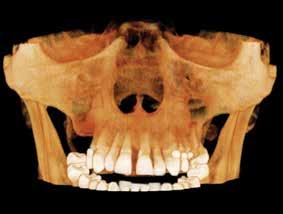

L-Q

LEGALLY MINE

LUMADENT INC.

MANGO VOICE

MEDILOUPES

MEDIT

MEDS 2U PHARMACY: EMERGENCY

DENTAL KITS